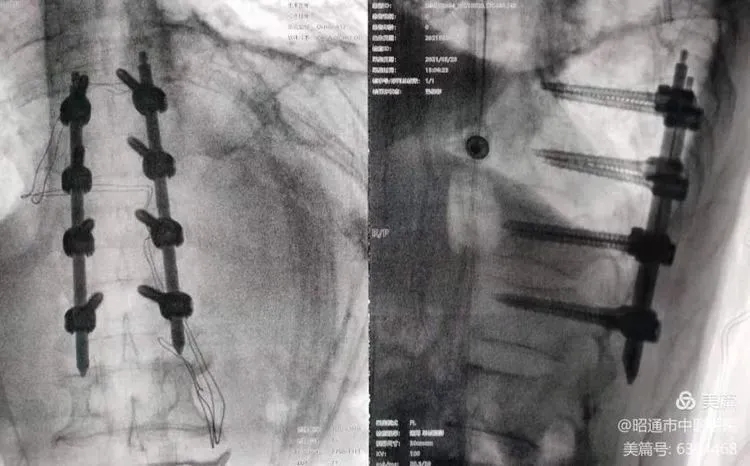

骨伤科运用天玑骨科手术机器人成功实施2例脊柱微创手术

近日,我院骨伤科主任訾成毅带领团队在天玑骨科手术机器人的辅助下,成功完成了两例胸椎骨折经皮椎弓根螺钉内固定术。其中一名患者胸11、12椎体Chance骨折,术中胸椎可能移位且置钉过程中也可能误入椎管引起脊髓损伤,借助天玑骨科手术机器人高精度与个性化手术规划的功能,精准、安全、微创地完成了手术。

天玑骨科机器人是北京积水潭医院联合北京天智航科技股份有限公司研发的基于术中实时三维图像的第3代骨科机器人,是一种基于术中3D图像进行手术空间映射和手术路径规划的机器人定位系统,在上颈椎、胸腰椎手术、经皮螺钉内固定治疗骨盆骨折和髋臼骨折等方面充分展现了其安全性高、创伤小、并发症少等优点。